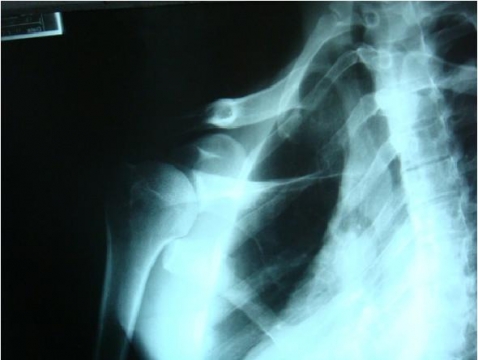

- RX: fratura da escápula

• Cintura escapular desnivelada, rebaixada à esquerda, com perda do contorno normal do ombro E